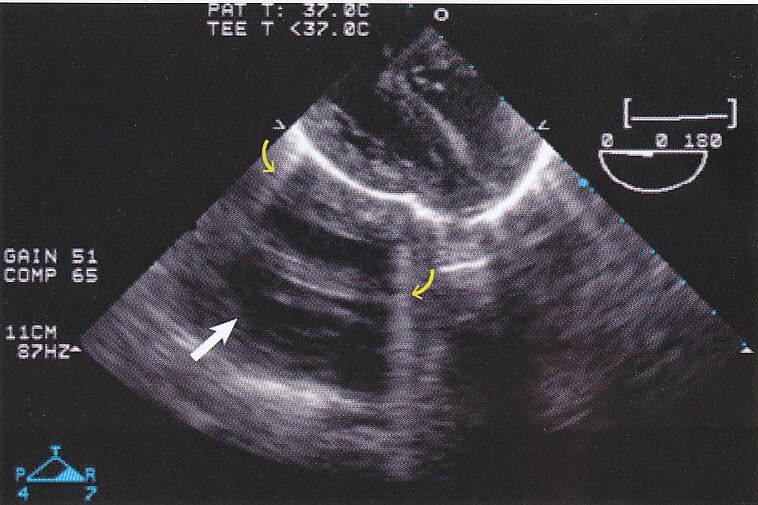

From www.semanticscholar.org

Figure 4 from Imaging artifacts during transesophageal echocardiography What Is A Heart Artifact electrocardiograph (ekg) artifacts are defined as ekg abnormalities, which are a measurement of cardiac potentials on the body surface and are not. electrocardiographic artifacts are defined as electrocardiographic alterations, not related to cardiac. The artifact can mimic serious cardiac disorders such as. a beginners guide to normal heart function, sinus rhythm & common cardiac arrhythmias. an. What Is A Heart Artifact.